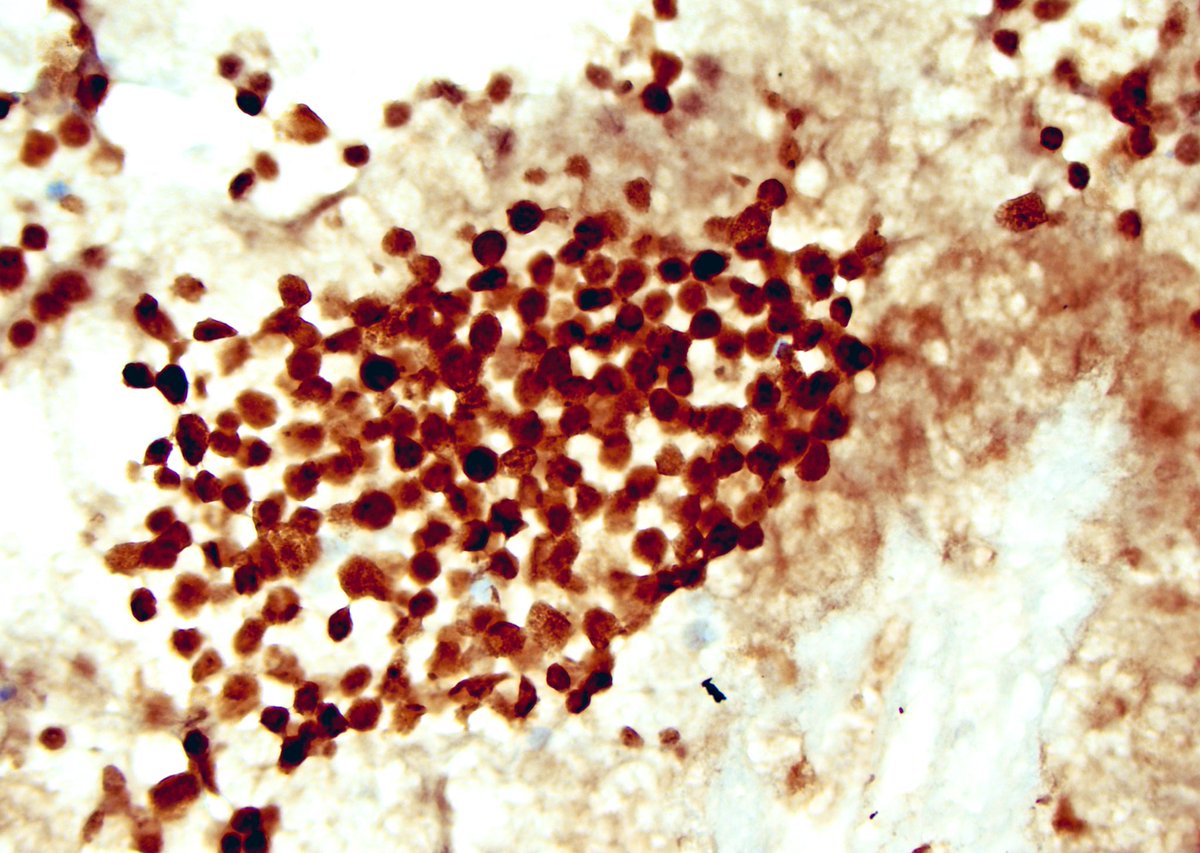

IHC and GPS seem parallel to me. It is hard to imagine life without them. They both help to take us to our destination however, we should know where the destination is. PHOX2B highlights metastatic neuroblastoma in bone of a kid. #CytoPro International Academy Cytology European Society of Pathology (ESP) #cytology

IHC and GPS seem parallel to me. It is hard to imagine life without them. They both help to take us to our destination however, we should know where the destination is.  PHOX2B highlights metastatic neuroblastoma in bone of a kid.  #CytoPro  <a href="/IACytology/">International Academy Cytology</a> <a href="/ESP_Pathology/">European Society of Pathology (ESP)</a> #cytology